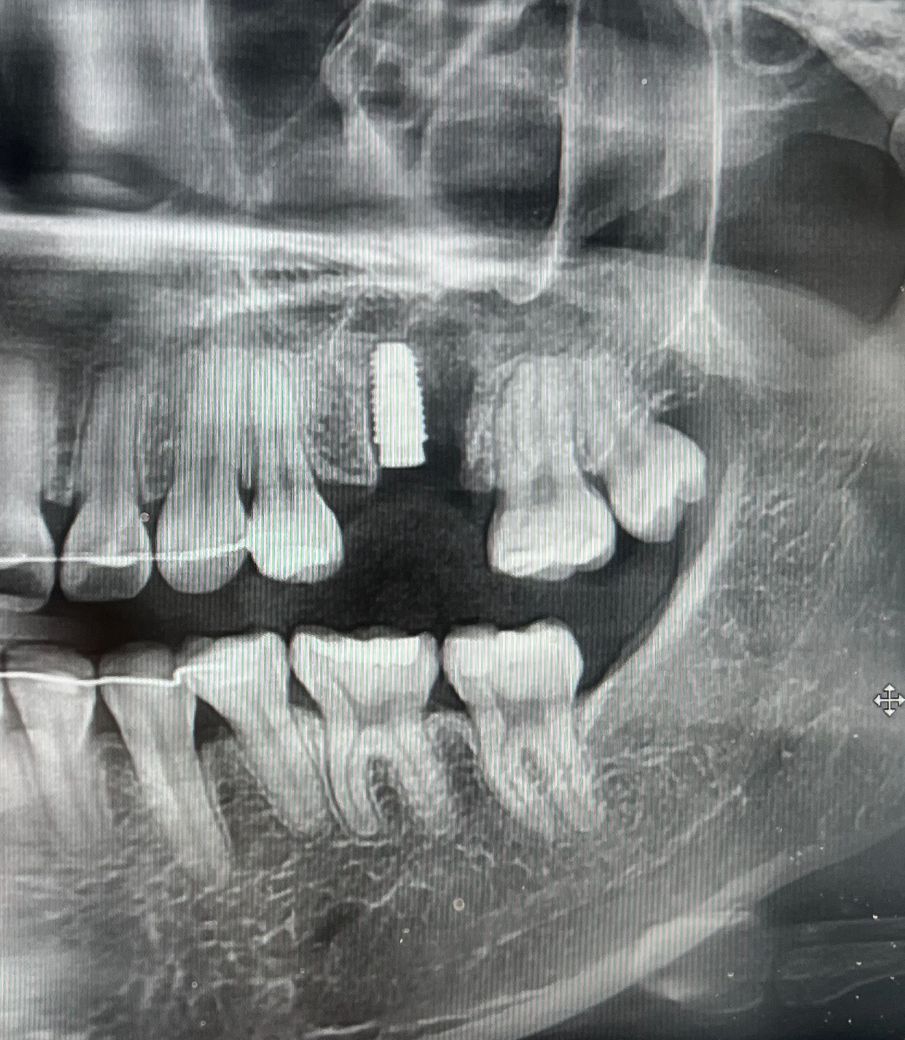

오스템 임플란트 상악동 거상술 식립 후

22일에 제목 그대로 상악동 거상술 했는데 임플란트가 보이지 않는데 원래 이런건가요?? 다른 분들 임플란트 식립한 사진 보면 임플란트가 보이는데 저는 보이지 않아서 걱정돼서요 정상적으로 잘 식립 된건가요?? 안 보이는 경우도 있나요?? 수술 당일 엑스레이와 현재 모습입니다

임플란트는 내부에 깊게 식립되어 보이지 않을수도 있습니다.

임플란트의 고정력이 약한경우에는 임플란트가 뼈에 잘 붙게 하기 위해서 잇몸안쪽에 안보이도록 해놓는경우도 있습니다 .

상악동 수술을 받은 경우에는 임플란트 수술후에 시간이 조금더 지나서 어버트먼트라고 하는 잇몸위로 나오는 구조물을 체결하기도합니다.

현재 뼈 안에 임플란트 뿌리를 심어둔 상태이고 그 뿌리의 뚜껑이 잇몸위쪽으로 튀어나오는 치유지대주 종류가 아니라 커버스크류 종류라 그렇습니다. 잇몸안에 있다고 보시면 됩니다.